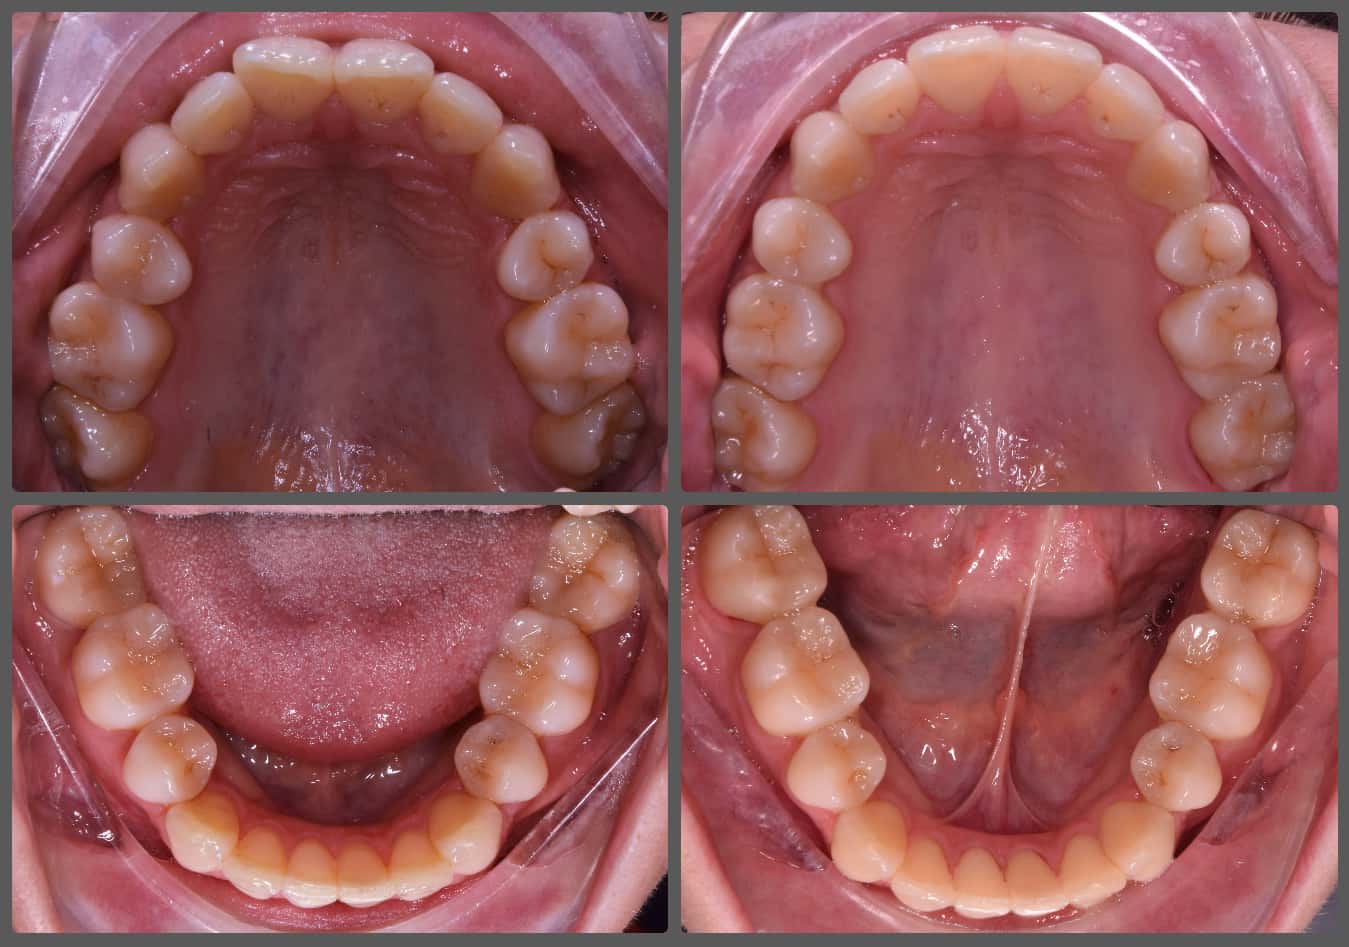

Extrém súlyos alsó-felső torlódása miatt jött hozzám fogszabályozási konzultációra Viki. A korábbi szakvélemények mindegyike foghúzással járt volna. Súlyosan eltolódott alsó-felső középvonalat, súlyos alsó-felső torlódást, mélyharapás, fogívszűkületet és a nyelv felé dőlő fogíveket diagnosztizáltam. Viki harapási és anatómiai adottságai miatt úgy ítéltem meg, hogy a kezelését foghúzás nélkül is végig tudjuk vinni. H4 önligírozó fogszabályzó készüléket ragasztottunk Vikinek, és a torlódott területeken tolórugóval csináltunk helyet a fogívből kiszorított fogaknak. A harapás harmonizálást és a mélyharapás korrekcióját intermaxilláris gumihúzással, valamint harapásemelőkkel végeztük. A teljes kezelés 26 hónapig tartott, melynek végére egy igazán gyönyörű, telt mosolyt sikerült Viki arcára varázsolni, mindemelett a szinte tökéletes oldalsó fogilleszkedést is megtartottuk, tovább javítottuk. Az ilyen látványos változások, páciens átalakulások miatt szeretem a legjobban a munkám!